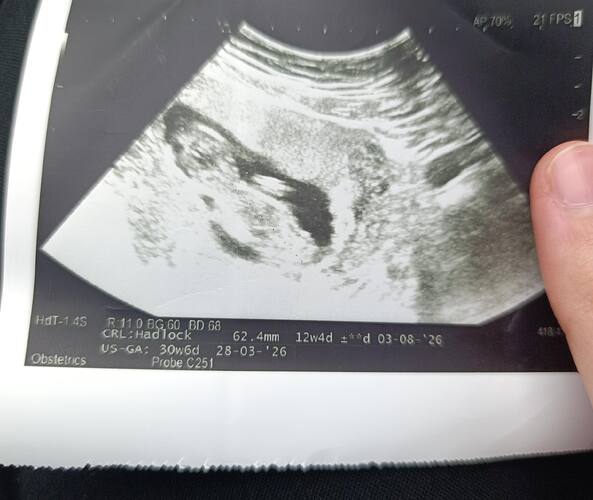

Kız dedi doktorum ![]()

Kız hissettim Allah tamamına erdirsın insallah

Evet kiza benziyo bence de![]()